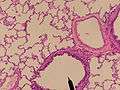

A lobule of the lung showing r. b respiratory bronchiole;al. d alveolar duct;a. s alveolar sac;'a' alveolus;

A pulmonary lobule is the portion of the lung ventilated by one bronchiole. Bronchioles are approximately 1mm or less in diameter and their walls consist of ciliated cuboidal epithelium and a layer of smooth muscle. Bronchioles divide into even smaller bronchioles, called terminal, which are 0.5mm or less in diameter. Terminal bronchioles in turn divide into smaller respiratory bronchioles which divide into alveolar ducts. Terminal bronchioles mark the end of the conducting division of air flow in the respiratory system while respiratory bronchioles are the beginning of the respiratory division where actual gas exchange takes place.